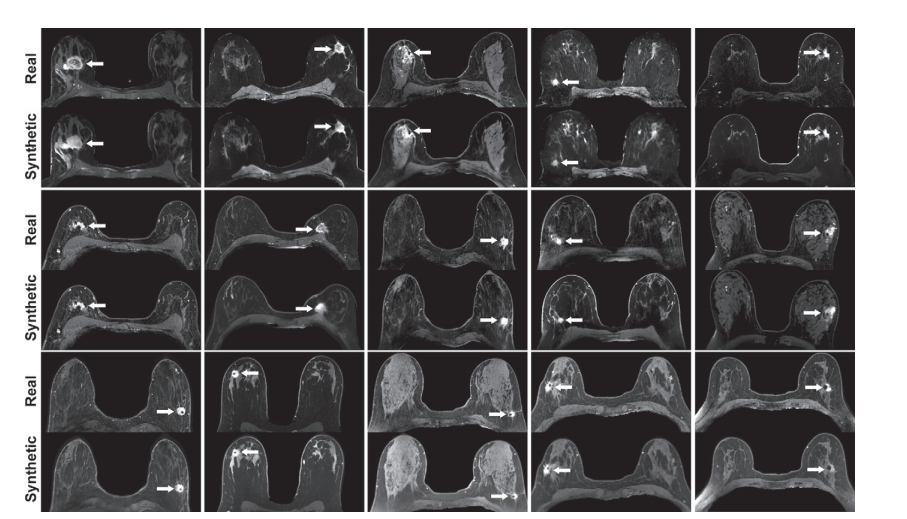

Figure 4: Real versus simulated (ie, synthetic) contrast-enhanced T1-weighted axial breast MRI scans of patients with invasive breast cancer. Pairs of real and simulated contrast-enhanced breast MRI scans from 15 patients with invasive breast cancer (arrows). Intrathoracic and extramammary structures were masked in all images.

图4: 侵袭性乳腺癌患者的真实对比增强T1加权轴向乳腺MRI扫描与模拟(即合成)对比增强T1加权轴向乳腺MRI扫描。15位侵袭性乳腺癌患者的真实和模拟对比增强乳腺MRI扫描对(箭头)。所有图像中的胸内和乳腺外结构均被遮挡。